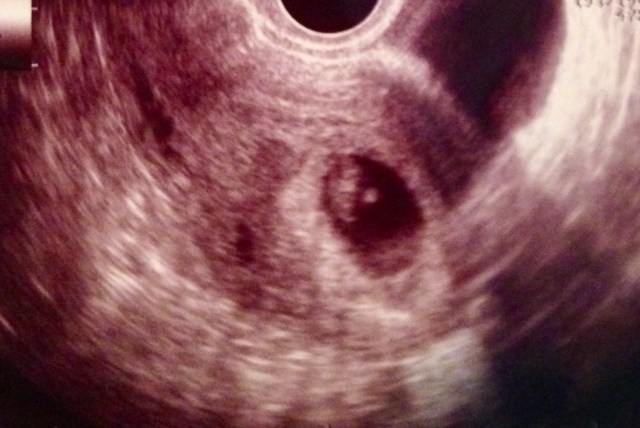

I entered into our second viable pregnancy on the cusp of a miscarriage. I had miscarried before, so I was not new to the feelings. However, this pregnancy I felt relaxed. Maybe that was because I was already 7 weeks along. Yep, I had gone through two full periods all while carrying this baby. Basically, by the time I found out I was pregnant, I was out of the “danger zone”. Or at least the danger zone as I had known it.

The news was shocking to say the least. I was at my OBGYN’s office for a birth control RX. The previous miscarry had been a lot on my husband and I. We had decided to take pre-cautions until we were sure we wanted to try for a second baby. Ironic that this was the day I saw the baby I absolutely couldn’t live without.

No symptoms, no signs of pregnancy. A different baby, a different pregnancy. It was then that I learned, sometimes when a woman miscarries, her body will begin to ovulate “twice a month”. Often your cycle will continue through the first couple months of pregnancy. Lots of surprises that day.